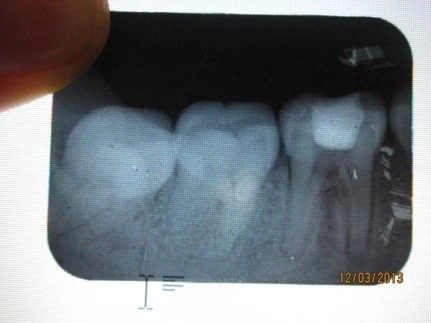

Thủng mặt ngoài thân, chân răng

Thủng sàn tủy

1. Sử dụng mũi khoan không đúng (mũi cắt mạnh: tungsten, mũi trụ kim cương). Không đổi sang mũi khoan endo Z khi đã vào buồng tủy.

2. Ấn mũi khoan mạnh về phía sàn tủy.

3. Tinh thần không thoải mái do đã mở sâu rộng mà không tìm được lối vào, không nắm cấu trúc giải phẫu ống tủy, hình thái hệ thống ống tủy bất thường.

4. Không phân biệt được trần và sàn tủy (ở bệnh nhân lớn tuổi trần và sàn tủy quá gần nhau or không nắm vững cấu trúc giải phẫu buồng tủy)

NHỮNG SAI SÓT TRONG MỞ TỦY thủng sàn tủy